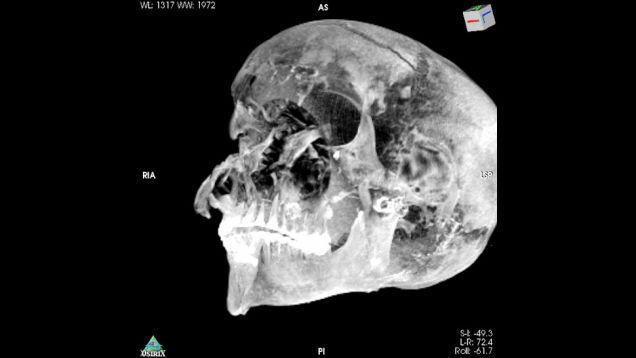

The forensic analysis of a 3,600-year-old mummy is providing fascinating new insights into a pivotal Egyptian pharaoh and the circumstances of his exceptionally violent death.

Source: Gizmodo – Seriously Gruesome Death of an Egyptian Pharaoh Detailed in New Study